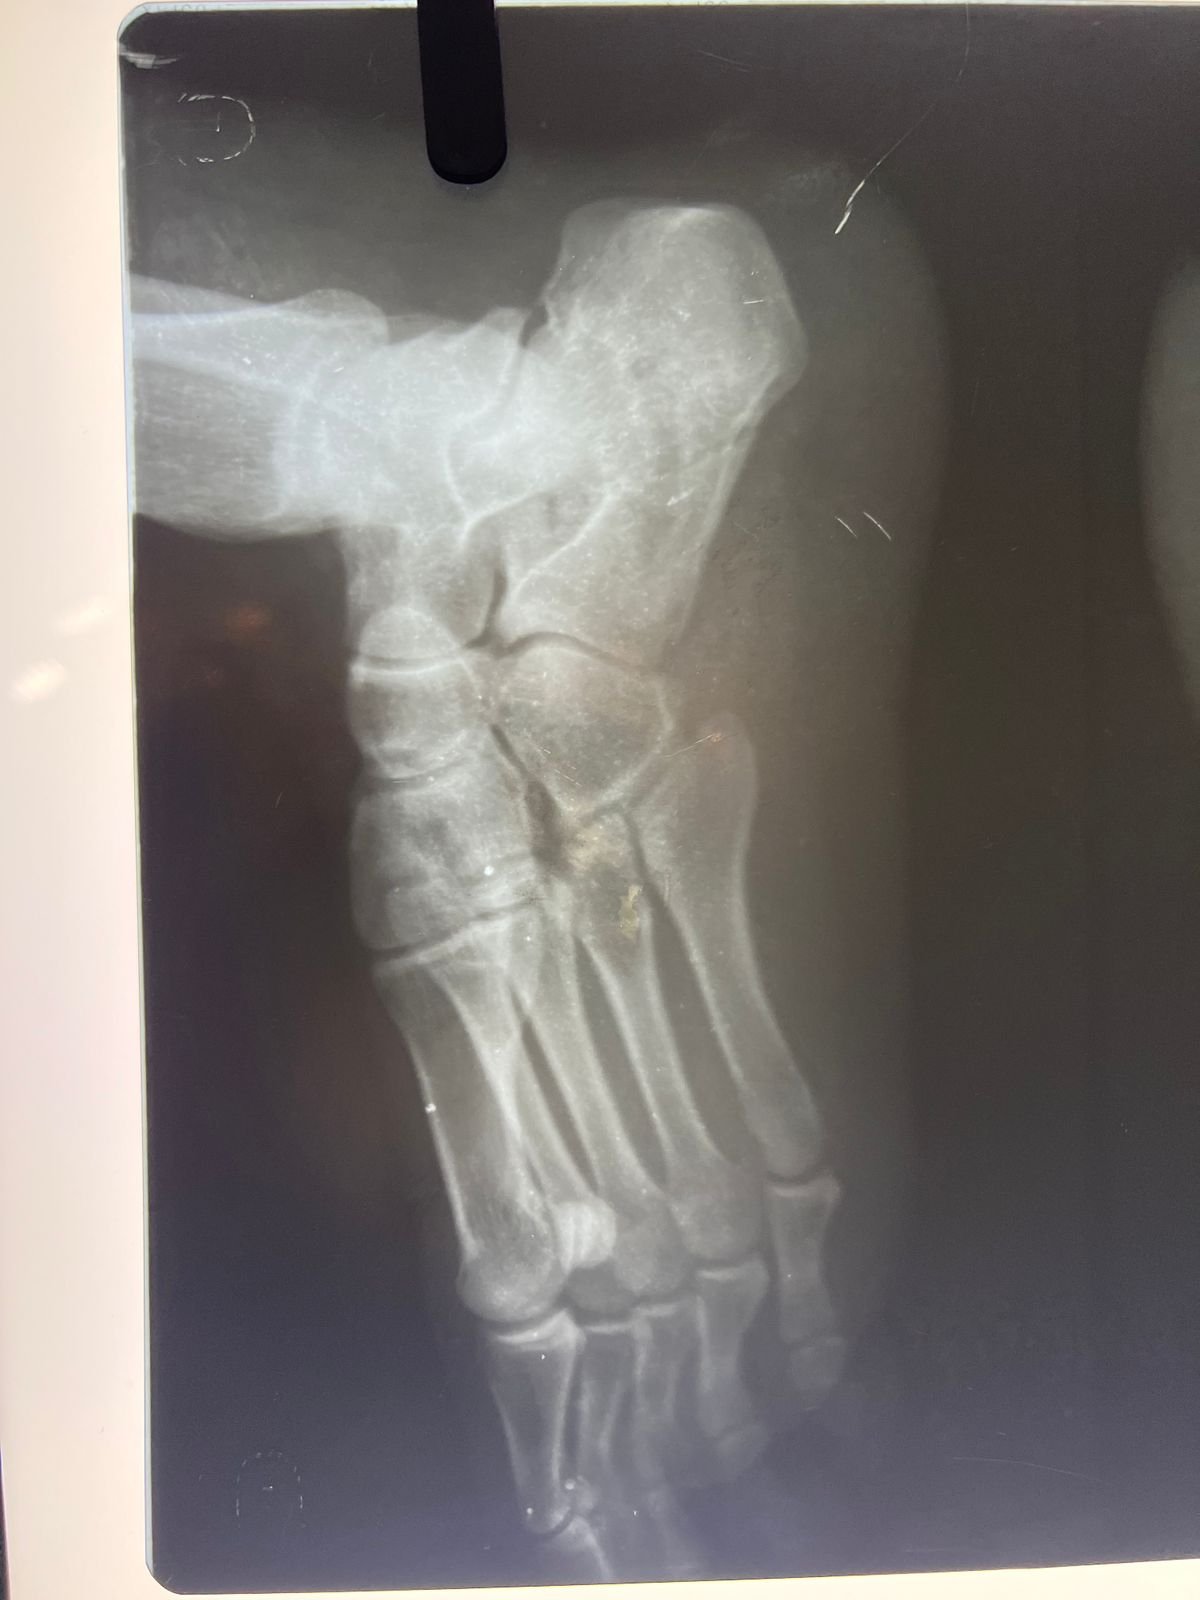

postop | Congenital foot deformity pre & post

Heal fracture pre & postop | Clavicle fracture pre &